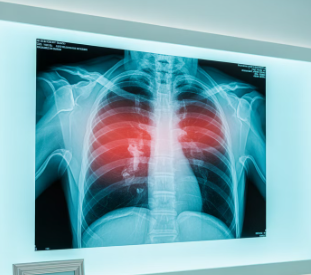

폐렴이 의심되면 보통 흉부 X-ray를 먼저 찍습니다. 필요할 경우 CT 촬영으로 더 정밀하게 확인하기도 해요. 혈액 검사로 염증 수치를 확인하고, 가래 검사를 통해 어떤 균이 원인인지 찾습니다. 정확한 진단을 위해서는 단순 증상만으로 판단하지 않고 여러 검사를 종합적으로 진행합니다.